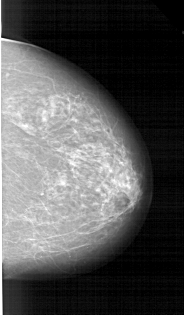

A_1214_1.RIGHT_CC

RIGHT_CC LINES 5341 PIXELS_PER_LINE 3121 BITS_PER_PIXEL 12 RESOLUTION 43.5 NON_OVERLAY